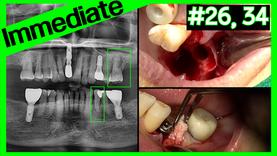

Immediate Implant Placement at the Posterior Region

Case Discussion

Dilihat 11